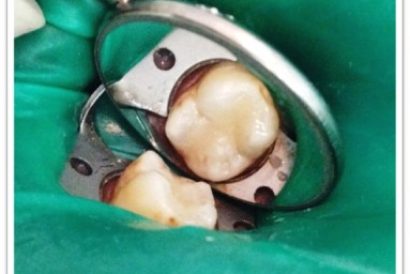

Patient Name:Chaitrali Patel

Tooth Involved :46

Diagnosis :Caries Involving Enamel And Dentin Approaching The Pulp : Sympotomatic Reversible Pulpitis

Treatment :Direct Pulp Capping With MTA

Restoration: Direct Composite Restoration Using Nanohybrid Composite

Before